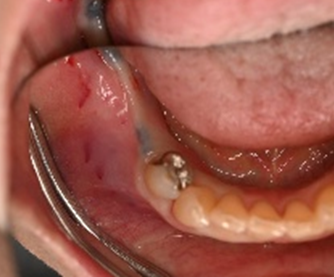

Before

赤丸は抜歯しました

【抜歯後】

【骨造成前】

【骨造成後】